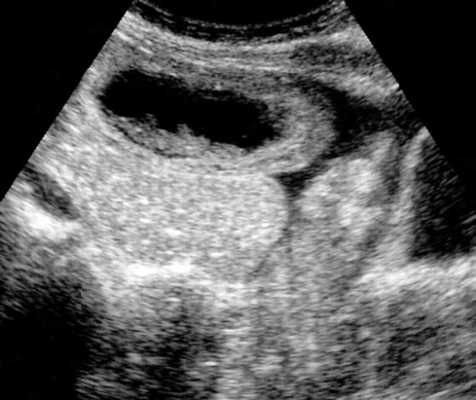

(г, д) На рентгенограммах выявлен симптом «штопора» — спиральная конфигурация 4-го отдела двенадцатиперстной кишки и проксимальной части тощей кишки.

б) Лучевая диагностика заворота тонкой кишки. При стандартной рентгенографии чаще выявляют неспецифические признаки, и она редко бывает информативной в диагностике. Симптом «штопора», известный как диагностический признак заворота средней кишки, отображает спиральную конфигурацию 4-го сегмента двенадцатиперстной кишки и проксимальной части тощей кишки, классически выявляемую при рентгенографии у детей, особенно у младенцев. Его можно визуализировать в переднезадней и боковой проекциях.